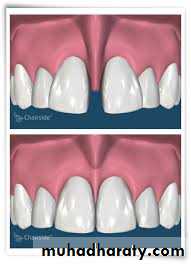

LIP SUPPORT – adequately supported

- unsupportedContour and appearance of the

vermillion border usually are alteredby tooth loss

Placement of anterior teeth

If the anterior teeth are set too far lingually or palatally, lips will lack the necessary support.

Unsupported lip